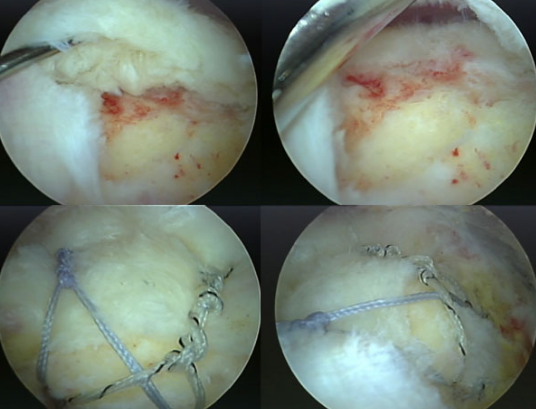

7. Como é a cirurgia?

A cirurgia é feita por artroscopia (mínima invasão). Passo a passo:-

- Limpeza do tecido doente]

- Preparação da área do osso

- Colocação de âncoras

- Sutura dos tendões rompidos

- Reparo anatômico da lesão